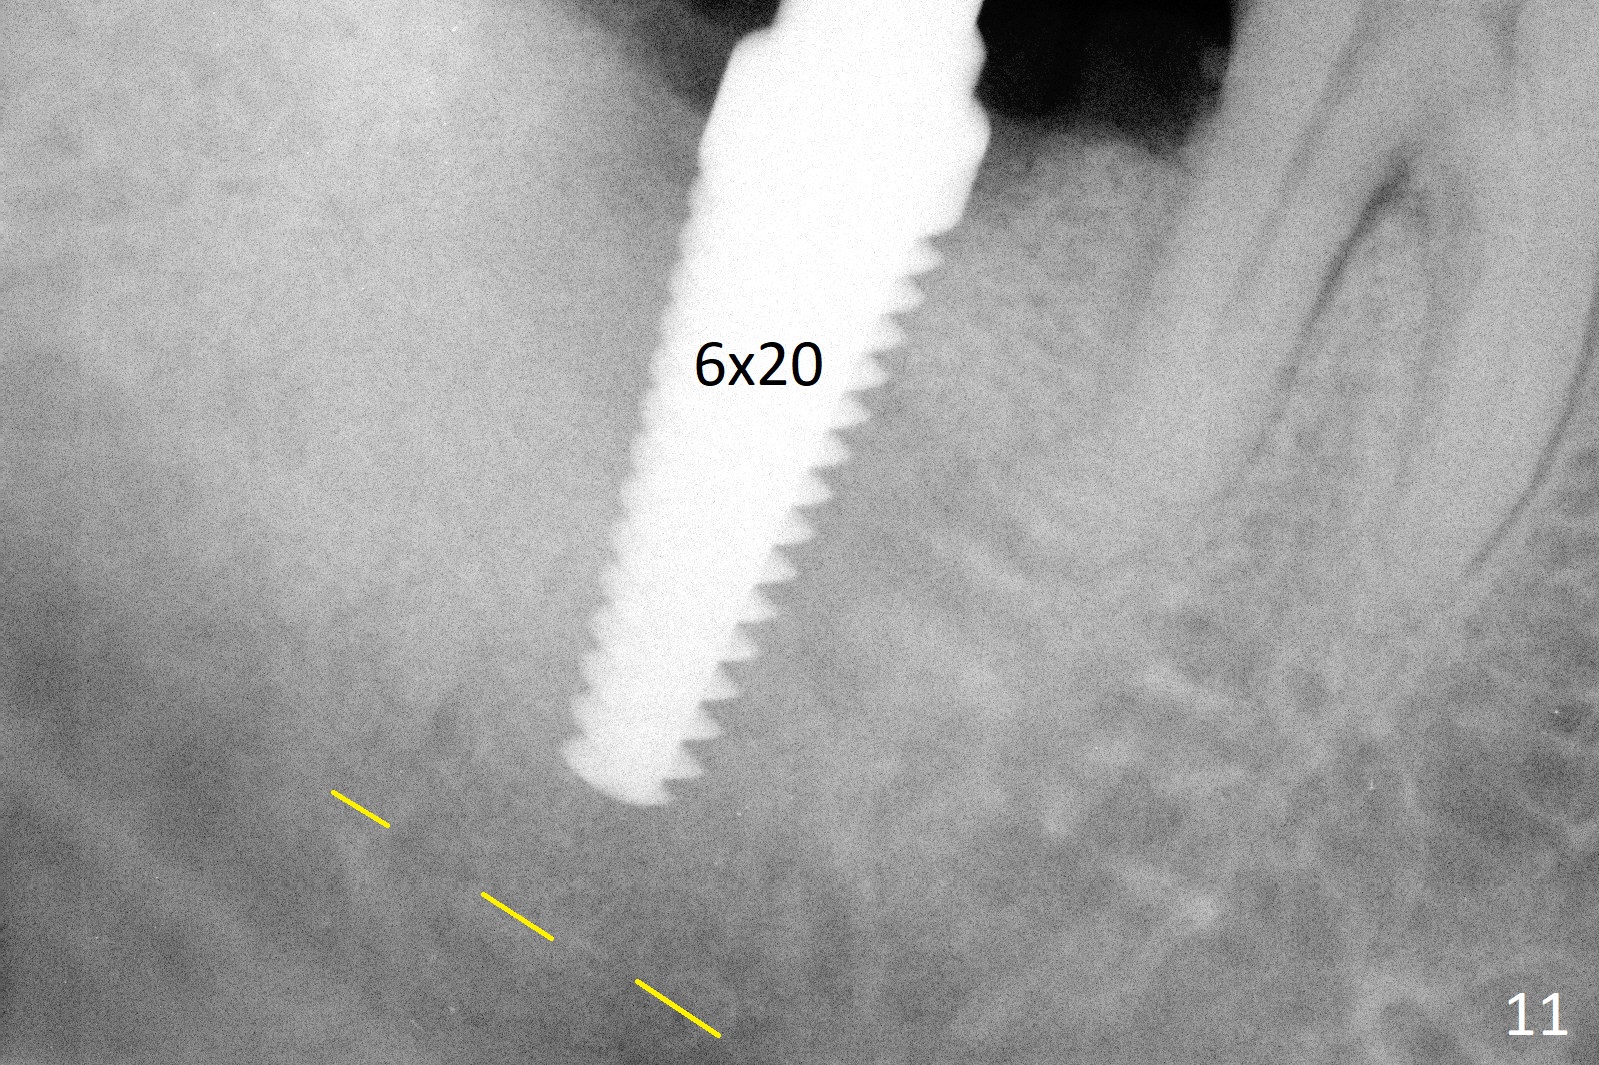

A 50-year-old man, a smoker, presents to clinic with pain of the tooth #15 with apparently occlusal trauma (Fig.1). Two years and three months after #15 extraction, he returns for #31 extraction (Fig.2) and socket preservation (Fig.3). The socket depth is 17 mm along the long axis of the socket 2.5 months post extraction (Fig.4, gingival level). Initial osteotomy is created in the mesial slope of the socket for 14 mm (Fig.5). After sequential osteotomy, a 6x17 mm tap is seated shallower (Fig.6) than the 2 mm drill (Fig.5). Following further osteotomy, a 7x14 mm implant is seated incompletely (Fig.7), which was not found intraop. The implant becomes loose with purulent discharge 19 days postop. The patient returns for 2nd placement 2 months post implant removal (Fig.8). Osteotomy is created probably in the mesial slope with 17 mm (bone level, Fig.9). After insertion of 5 (Fig.10) and 6 (Fig.11) x20 mm taps (tissue level), a 6x20 mm tissue-level implant is placed with clearance from the Inferior Alveolar Canal (Fig.12 yellow dashed line). The implant is restored 8.5 months postop (Fig.13) without bonding 5 mm 0 degree unipost. The crown dislodges 4 months post permanent cementation. Still the patient complains of small crown without occlusal contact. Impression is taken for a new normal-sized crown. The new crown becomes loose 1 year 9 months post cementation (Fig.14). The teeth #14 and 15 remain unrestored.